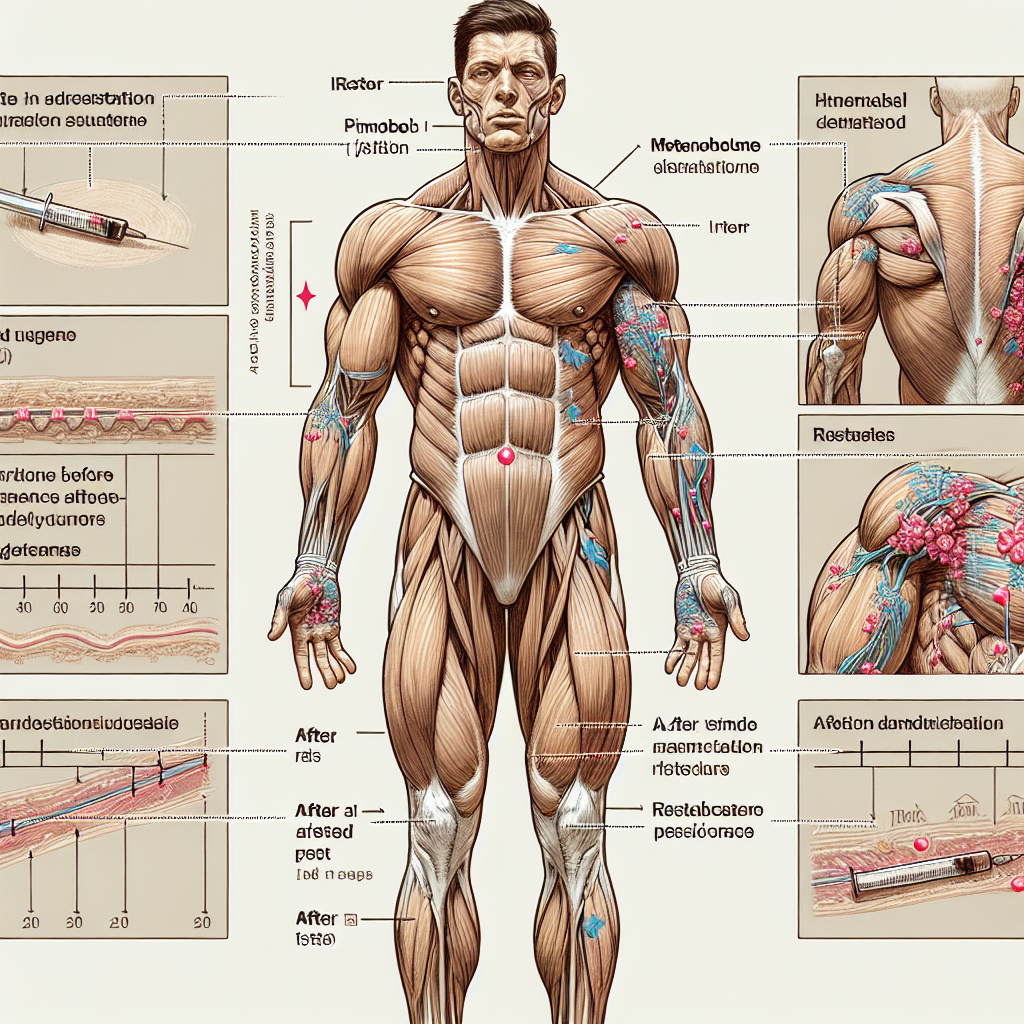

Después de suspender el uso de Primobolan inyectable, es probable que se produzcan cambios hormonales en el cuerpo. Estos cambios pueden variar de persona a persona y dependerán de factores como la dosis utilizada, la duración del ciclo y la sensibilidad individual.

Uno de los cambios más comunes es una disminución en los niveles de testosterona en el cuerpo. Esto puede resultar en síntomas como fatiga, pérdida de masa muscular, disminución del deseo sexual y cambios de humor. Estos síntomas pueden ser más pronunciados en aquellos que han utilizado dosis más altas o han utilizado Primobolan durante períodos prolongados.

Otro cambio hormonal que se puede esperar es un aumento en los niveles de estrógeno. Esto se debe a la conversión de testosterona en estrógeno a través de la enzima aromatasa. El aumento de los niveles de estrógeno puede causar retención de agua, ginecomastia (crecimiento de tejido mamario en hombres) y otros efectos secundarios relacionados con el estrógeno.

Además, la supresión del eje hormonal puede afectar la producción de otras hormonas, como la hormona luteinizante (LH) y la hormona folículo estimulante (FSH). Estas hormonas son responsables de estimular la producción de testosterona en los testículos. Por lo tanto, su supresión puede tener un impacto en la recuperación de los niveles de testosterona después de suspender el uso de Primobolan.